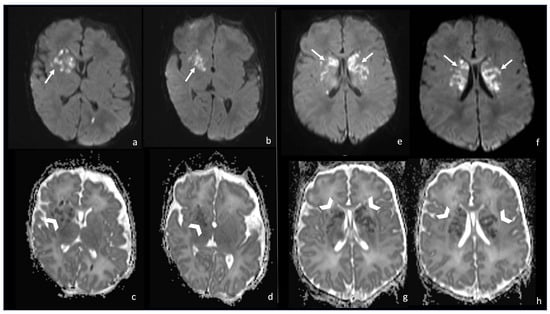

7.1. Group B Streptococcus

- Choi, S.Y.; Kim, J.-W.; Ko, J.W.; Lee, Y.S.; Chang, Y.P. Patterns of Ischemic Injury on Brain Images in Neonatal Group B Streptococcal Meningitis. Korean J. Pediatr. 2018, 61, 245–252. [Google Scholar] [CrossRef] [PubMed]